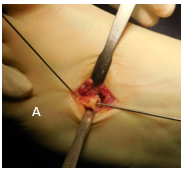

Se utilizó un abordaje dorsal sobre el cuarto metatarsiano, una osteotomía transversal a nivel de la metáfisis proximal del mismo, (guiado por fluoroscopio) para obtener un mayor contacto y dar más estabilidad al injerto. Se coloca un injerto tricortical de cresta ilíaca que se estabiliza con un alambre de Kirshner como tutor endomedular y se retira a las 6 semanas. Esta aguja de Kirschner se coloca de proximal a distal intra focal. Saliendo por la planta y de forma retrógrada se coloca en la posición deseada, fijando el injerto. Se realiza una zetaplastia del tendón extensor largo del cuarto dedo. La técnica se describe como en un tiempo, con un alargamiento promedio de 1.3cm, restaurando la función del pie con menos complicaciones. (Figura 3).

Figura 3: A: Abordaje dorsal centrado en el 4o. metatarsiano. Liberación de los músculos interóseos. A: colocación de injerto tricortical de cresta ilíaca. Previo se realizó osteotomía a nivel del osteotomía a nivel del 4o.

A nivel del cuarto metatarsiano se efectúa capsulotomía de la metatarsofalángica, zetaplastia del tendón extensor largo y corto del cuarto radio, osteotomía y colocación de injerto con una aguja de Kirshner que se coloca de proximal a distal intrafocal. Saliendo por la planta y de forma retrógrada se coloca en la posición deseada, fijando el injerto; se inmoviliza la articulación metatarsofalángica con Kirshner para prevención de luxación de ésta. Los alambres se retiran a las 6 semanas. (Figura 9 y 10).

Figura 10 A y B: Se realiza un abordaje dorsal en el segundo espacio. Osteotomía de ambos metarasianos. Liberación de cápsula y zetaplastia de extensores. Abordaje sobre el cuarto metatarsiano. Osteotomía y colocación del injerto.